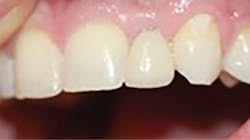

After a three-month integration period, final impressions were taken for a screw-retained crown. The procedure was noneventful, and not only was the patient happy having a provisional tooth, but the relief offered with a permanent fixed solution changed his entire outlook (figures 5 and 6).

Figure 6: Final implant restoration

A 1.8 mm x 14 mm Anew implant (Dentatus) was selected, and a surgical guide was fabricated for a flapless approach. In this instance, a healing cap was placed, and the existing flipper was relieved to address financial concerns (figures 9 and 10). A screw-retained crown was fabricated three months post insertion (figures 11 and 12). The patient reported no postoperative discomfort, and the case remains successful, as shown in the two-year postoperative x-ray (figure 13).

Figure 11: Final restoration

Figure 12: Final crown seating